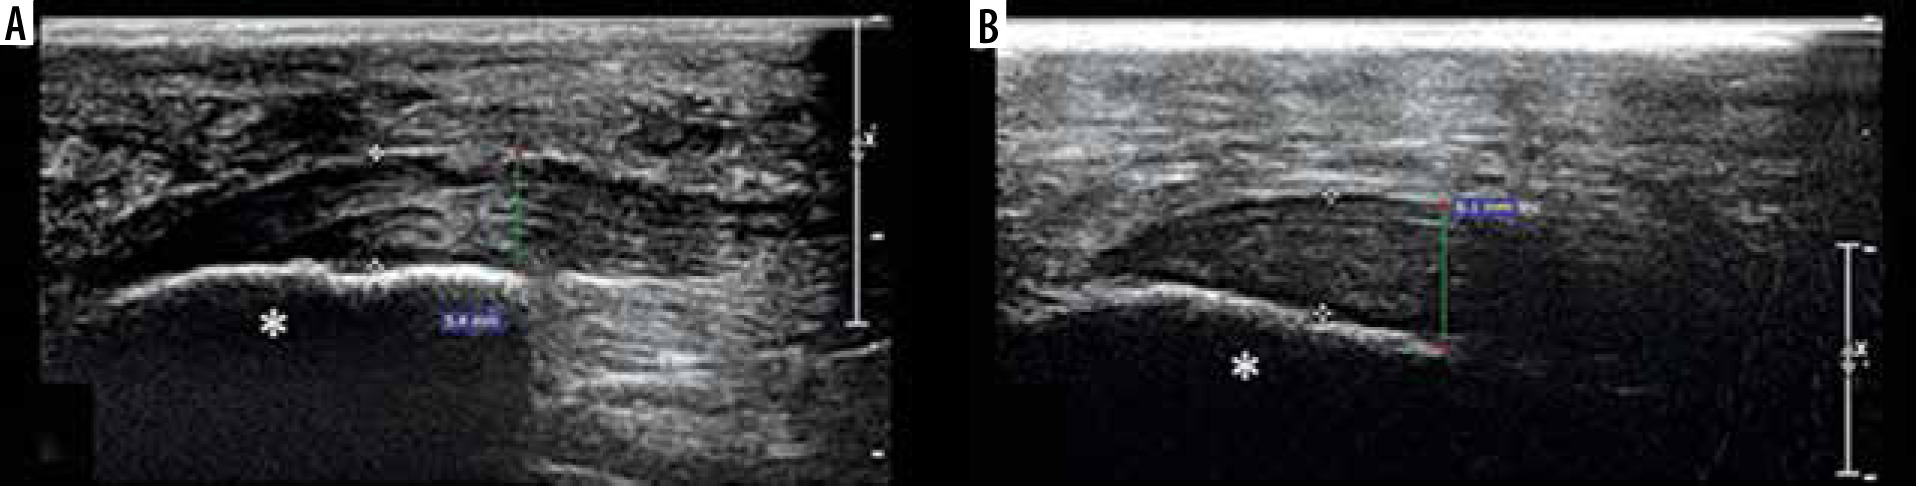

Figure 3

Longitudinal ultrasonographic images of the plantar fascia of 2 patients, a 50-year-old female (A) and a 60-year-old male (B) show thickening and hypoechogenicity near the insertion on the calcaneus with loss of striated appearance (asterisk)